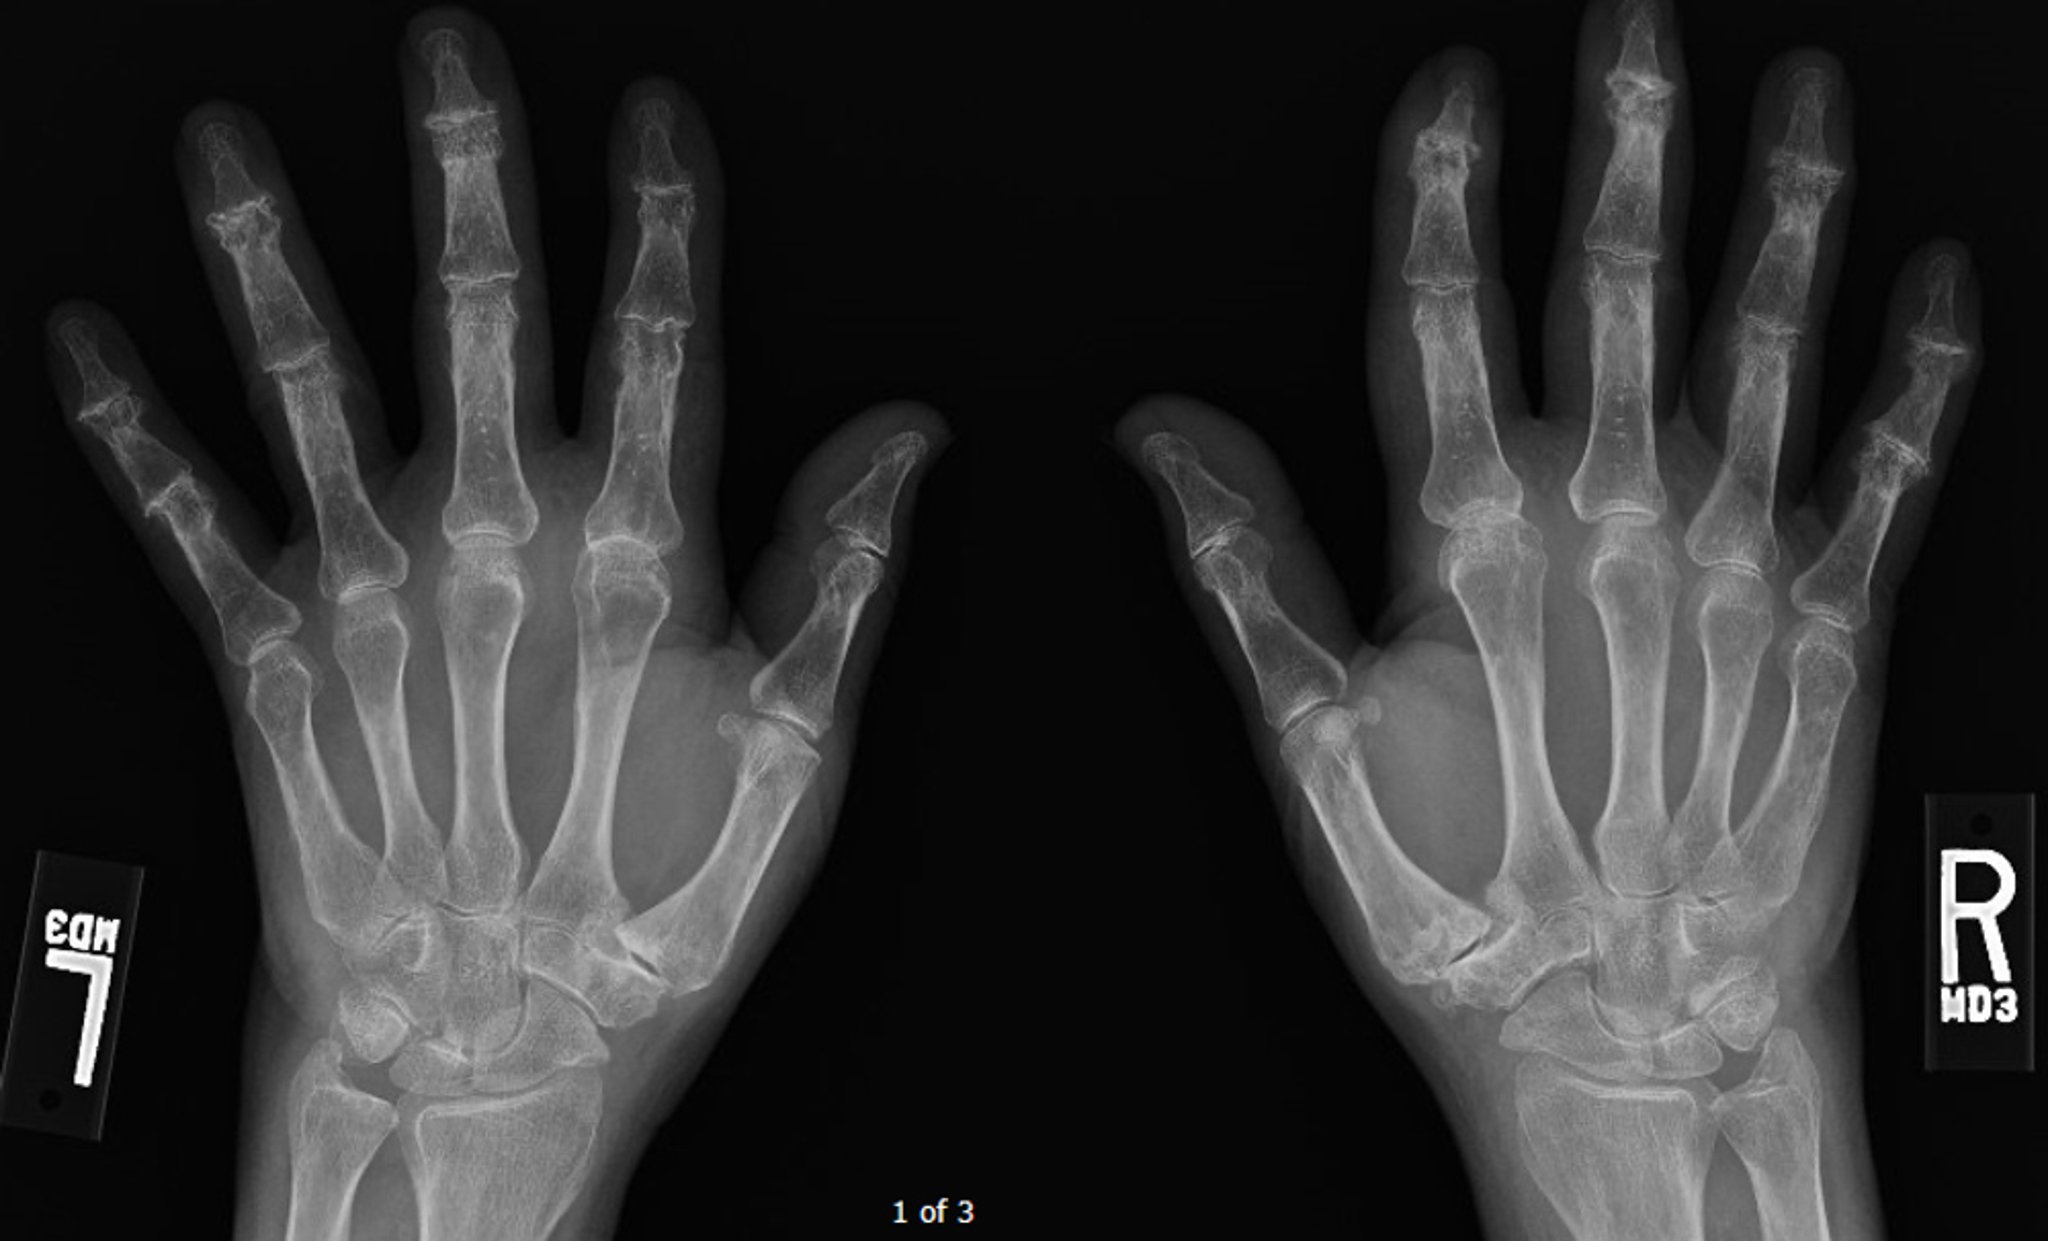

Artrosis erosiva

Esta radiografía muestra artrosis difusa avanzada, sobre todo en las articulaciones interfalángicas distales, donde pueden observarse algunas erosiones centrales.

Image courtesy of Kinanah Yaseen, MD.